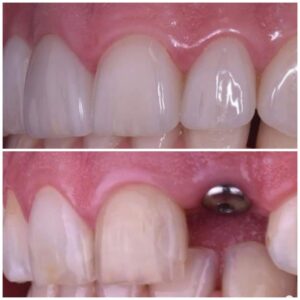

جماليات زراعة الأسنان

يتم تخطيط وتنفيذ إجراء زراعة الأسنان بعناية لضمان أن ترميم الأسنان يبدو طبيعيًا في الشكل واللون والمكان. نعطي الأولوية لراحة مرضانا بالإضافة إلى الجماليات. وهذا يتطلب مزيجًا مثاليًا من العبقرية الفنية والجراحية. لذلك ، يتم تنفيذ جميع حالات الزرع لدينا من قبل فريق من أطباء الأسنان التجميليين وأخصائي زراعة الأسنان.